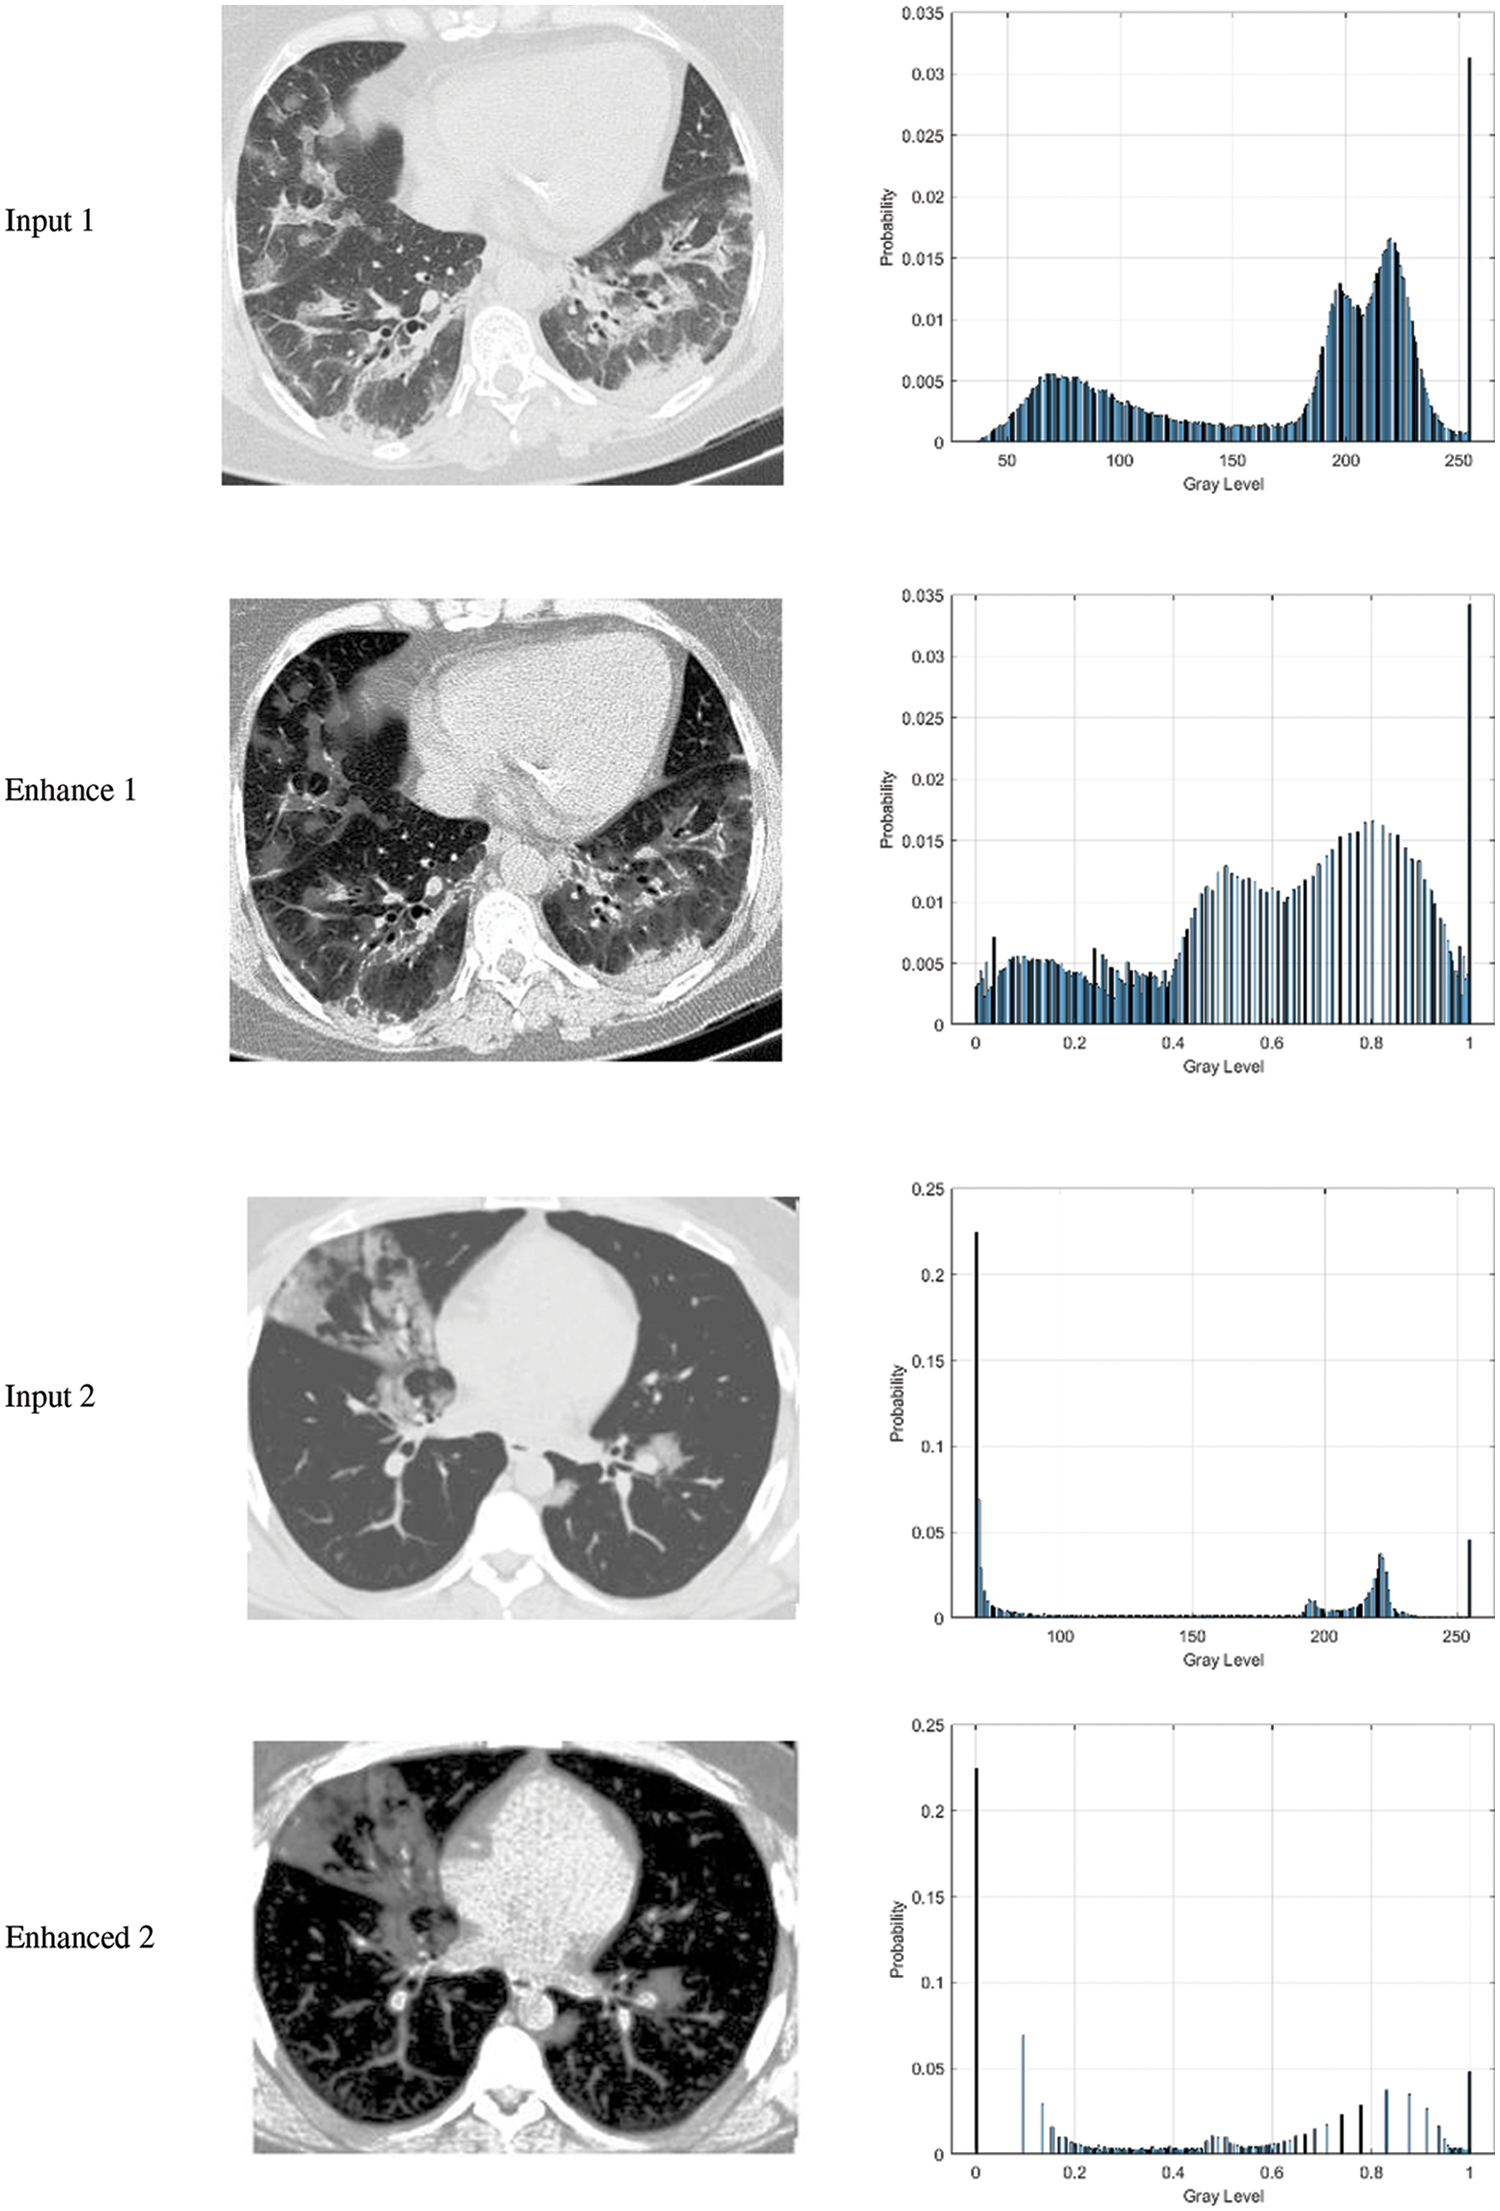

The qualitative results of the proposed MLCS image enhancement are shown in Fig. 2. The figure includes the input images, the enhanced images, as well as the histogram plot. It is clear from Fig. 3 that the input image pixel probability looks dense, while the enhanced image pixel probability looks distributed. This indicates that the image's contrast has been improved by the proposed MLCS method.

Figure 2: The output of the enhancement proposed algorithm along with histogram analysis for CT scans images